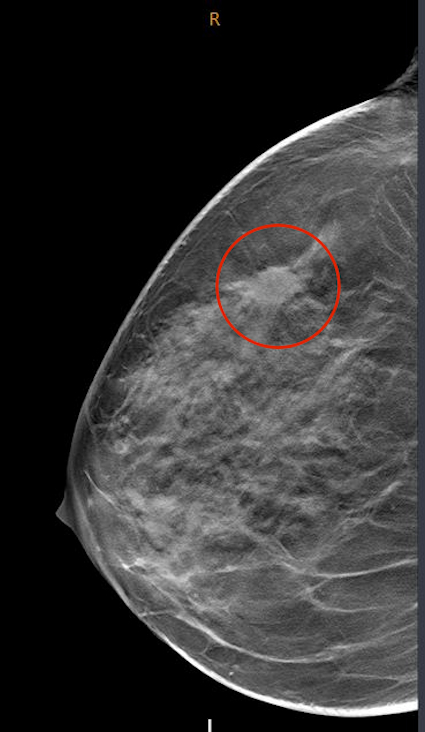

Eine halbe Stunde später folgt das Arztgespräch. Ich soll mich erst einmal auf die Liege legen, und der Arzt untersucht meine beiden Brüste und Achseln nochmals gründlich mit dem Ultraschallgerät. Sehr gut, dass gleich eine Tomosynthese gemacht worden sei… denn mit der bloßen Mammographie hätte sich mein Tumor nicht darstellen lassen! Doch da ist er, ich wisse es ja wohl schon… da ist ein Tumor in meiner rechten Brust… sieht nicht gut aus, und die fünf Lymphknoten in der Achsel sind auch befallen!

Tomosynthese der Brust mit markiertem Brustkrebs